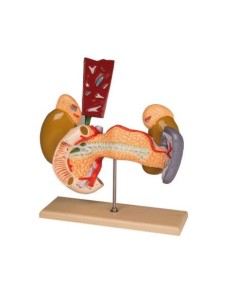

Modèle de maladie de l'articulation de la hanche 3B Scientific 1019506